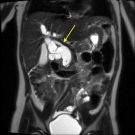

A 3-year-old girl presented to the emergency department with abdominal pain of 1 week’s duration. She also had had nonbloody and nonbilious emesis. She had a history of chronic constipation.